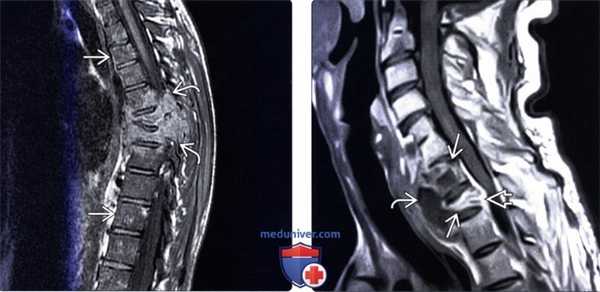

(Слева) Диффузное патологическое снижение интенсивности Т1-сигнала (кокцидиомикоз) отражает диффузную анемию и гиперплазию ± инфильтрацию костного мозга. Обратите внимание на деструкцию тел и задних элементов среднегрудных позвонков с распространением процесса на паравертебральные ткани и сохранением межпозвонковых дисков.

(Справа) Сагиттальный срез, Т1-ВИ с КУ (кокцидиомикоз: превертебральный абсцесс, характеризующийся периферическим контрастным усилением сигнала, на фоне хронического течения инфекционного процесса. Тела С7 и Т1 позвонков разрушены, при этом межпозвонковые диски относительно сохранны, в вентральной части эпидурального пространства определяется флегмона.

(Слева) Рентгенография локтевого сустава в ПЗ проекции: литический очаг с четким контуром в средней части зоны надмыщелка, биопсия доказала бластомикоз. Очаг имеет четкие контуры, края не склерозированы, с периоститом или склеротической костной реакцией.

(Справа) Рентгенография в ЗП проекции: пациент с септическим артритом, вызванным споротрихозом. Отмечается значительное сужение лучезапястного канала, с несколькими очагами деструкции с четким контуром. В отличие от других грибковых инфекций, споротрихоз чаще приводит к септическому артриту, чем к остеомиелиту. (Слева) Фронтальная Т2ВИ МР-И при диссеминированном кокцидиомикозе: многоуровневое вовлечение позвоночника и обширная паравертебральная флегмона. Обращает на себя внимание объем распространения и относительная сохранность межпозвонковых дисков.

(Справа) Рентгенография в ПЗ проекции, выполненная у взрослого пациента с кандидозным септическим артритом после операции на передней крестообразной связке пять лет назад: определяются истончение хряща, краевые эрозии большеберцовой кости и деминерализация. Аспирация доказала наличие активной инфекции, несмотря на два года лечения. Характерна малая степень реактивных изменений.